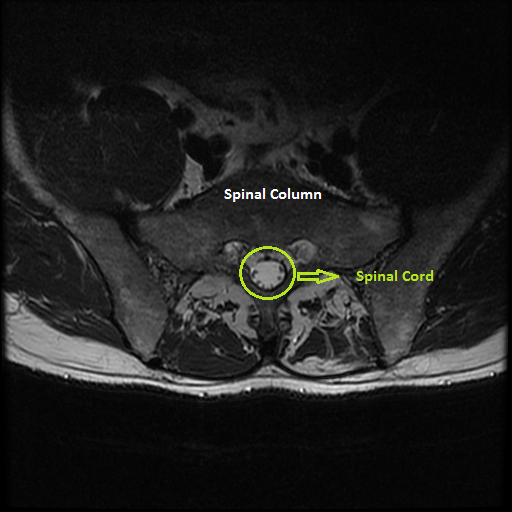

2.5.1 Detecting the spinal column with reference to the spinal cord

The spinal column is not consistent in size and shape across different MR Images. In contrast, the spinal cord is relatively consistent in size, shape and intensity level across different MR images.

Refer to caption

Figure 6: The spinal column and spinal cord

The following steps are used to detect the center of spinal column with reference to the center of spinal cord:

Step 1: A central patch encompassing the spinal column and spinal cord is initially cropped from the input image. The central patch is used to avoid fat regions, while using intensity thresholds to detect the spinal cord, which is the brightest region in the cropped patch.

Step 2: Based on empirical investigation, an optimal threshold level (Otsu’s global threshold + 0.2) is used to detect the spinal cord over different MR Images. Using this threshold level the spinal cord is automatically detected in the process of grayscale to binary image conversion.

Step 3: After detecting the spinal cord region, the centroid of the spinal cord is calculated.

Step 4: The center of the spinal column is approximately fixed 55 pixels above the center of spinal cord. This value was selected based on experiment results and after testing across different images.

The evaluation of this method was carried out by manually cropping the spinal column and calculating the centroids. The centroids obtained by the manual method were compared to centroids calculated from automatically detected spinal columns. This method is quick and precise, but for a small number of images there are slight variations (upto ±plus-or-minus\pm 7 pixels in X-coordinate and upto ±plus-or-minus\pm 15 pixels in Y-Coordinate) in the automatically detected center of the spinal column when compared to the actual center of spinal column. However, these slight variations do not affect the reference for region-wise fat quantification.